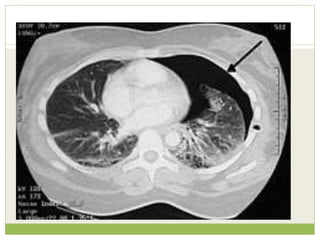

๏‚— Interpretation in view of clinical details

๏‚— Cancer - Smoker with weight loss and left apical

consolidation/mass and no clinical features of

infection

๏‚— Phrenic nerve palsy - Increased shortness of

breath and raised left hemidiaphragm

๏‚— Brachial plexopathy - Arm pain and axillary soft

tissue swelling